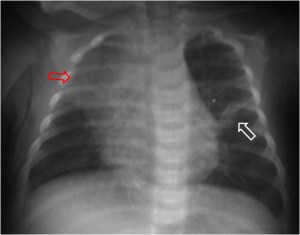

SIGNO DEL CORAZÓN PEQUEÑO

Signo de neumopericardio a tensión en la radiografía posteroanterior o anteroposterior de tórax. El neumopericardio es un hallazgo infrecuente que puede ocurrir en pacientes con traumatismo torácico. El signo del corazón pequeño consiste en una disminución del tamaño de la silueta cardiaca (como consecuencia del aumento de presión en el espacio pericárdico) y se acompaña de signos hemodinámicos de taponamiento cardíaco.

En la imagen, un caso de neumopericardio en un cadáver. Las radiodensidades puntiformes del hemitórax izquierdo corresponde a múltiples perdigones . Las flechas blancas marcan el contorno pericárdico y las rojas el cardiaco. Entre ambas, la zona radiolucente corresponde al neumopericardio.